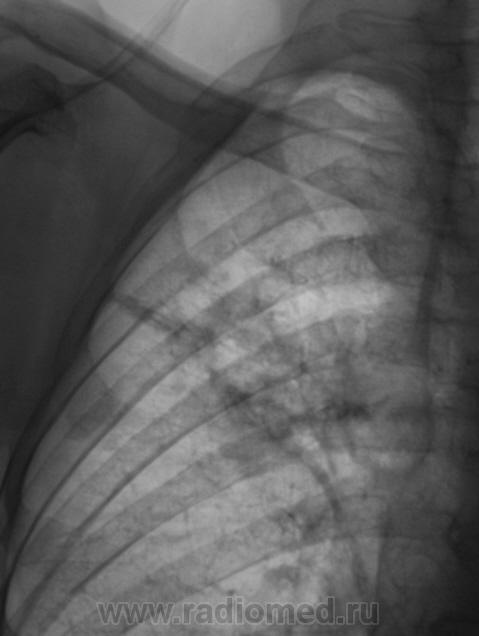

И откуда он берется? Очередной контроль после флюорографии.

Контроль передвижного флюорографа.

Сегодня дообследовали.

да тубркулеза у Вас хватает!

Но может оказаться и пневмонией..

Не оказался "пневмонией". Сегодня пришел коллега фтизиатр записать изображения на диск, посылает пациента в ОПТД, палки найдены.